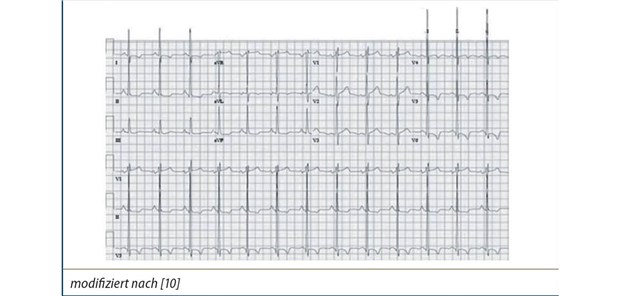

Abb. 1: EKG eines Patienten mit schwerer Mitralinsuffizienz mit linksventrikulärer Hypertrophie und linksatrialer Vergrößerung

Das EKG: Unterstützend bei Diagnose und Therapieplanung